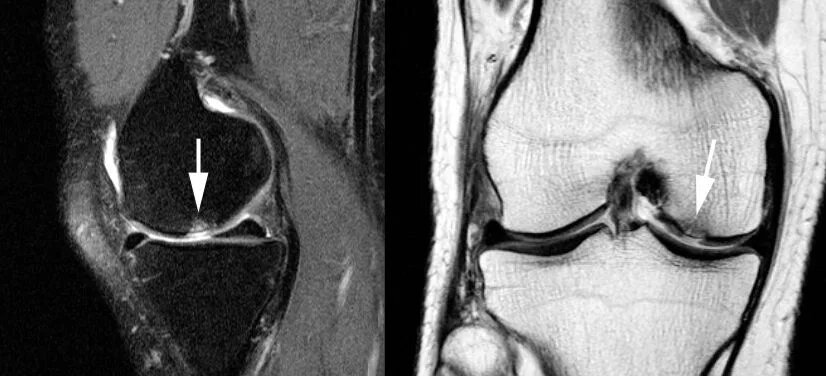

Характерная особенность: при артрозе на рентгене или МРТ видны дегенеративные изменения — сужение суставной щели, костные разрастания.

• Снимки (рентген, МРТ, УЗИ)